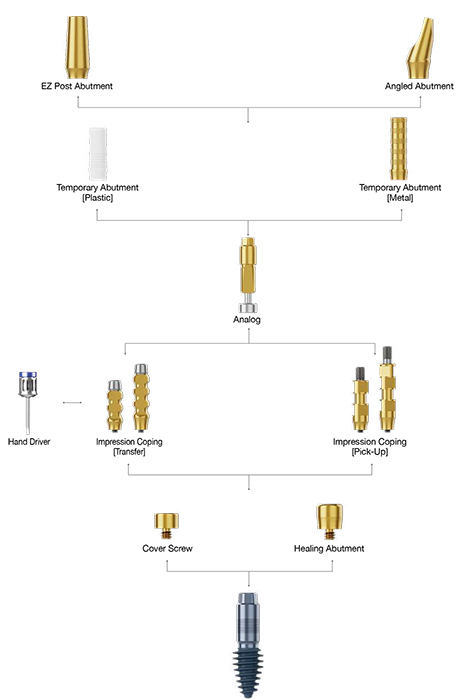

Abutment placement

The abutment is the connecting element between the crown and the implant.

The abutment is connected to the implant during or after the healing period, depending on the stability of the implant that gradually integrates with the surrounding bone to create a strong and lasting foundation.